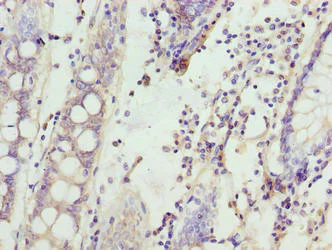

Immunohistochemistry (Formalin/PFA-fixed paraffin-embedded sections) staining human colon cancer using ab237532 at 1/100.